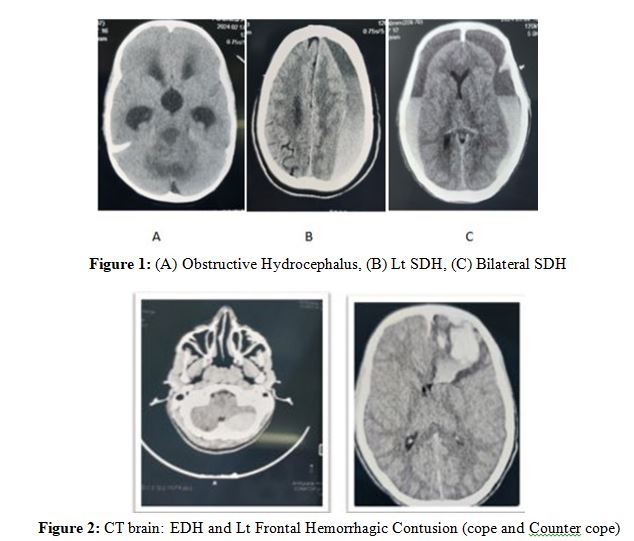

Results: During the period of this study, we made some changes in techniques and treatment strategies for treating patients with neurosurgical problems. Our data revealed, 18 patients were presented with extra-dural haemorrhage (EDH), depressed fracture was detected in 42 of the patients, and hydrocephalus 12, abscess 5, tumor were 8, and sub-dural haemorrhage (SDH) was encountered in 41 patients.

During the period of this study, we made some changes in techniques and treatment strategies for treating patients with neurosurgical problems. This study included 136 patients, male were 111 (81.6%), female were 25 (18.4%). The most frequent age group was ranging from 11 to 20 years which was detected in 18.4% of the patients (Table 1). Regarding diagnosis of the patients, sub-dural haemorrhage (SDH) was encountered in 41 patients (30.1%), the sub classes of SDH showed that, patients with acute SDH were 6 (14.6%), sub-acute were 17 (41.4%) and chronic were 19 (46.3%). Our data revealed, 18 patients were presented with extra-dural haemorrhage (EDH), depressed fracture was detected in 42 of the patients, and hydrocephalus 12, abscess 5 and tumor were 8 (Table 2). In this study 124 (91.1%) of the patients were recovered Immediately from anesthesia.